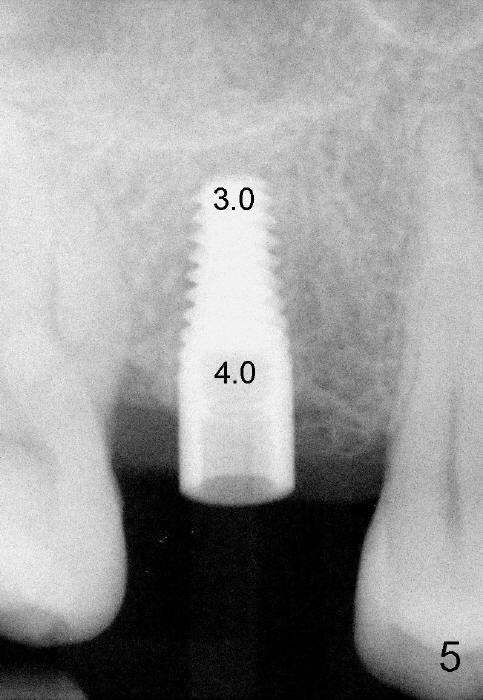

The 42-year-old lady is a dental phobic. The tooth #3 (residual root) is extracted 3.5 years ago. Finally she returns for implant (Fig.1). The mesiodistal space allows to place a 5x14 mm implant (Fig.2). Bone density is felt low when a 1.6 mm pilot drill is used. Bone condensation proceeds with bone expanders 2.6 mm (Fig.3) to 3.8 mm (Fig.4) 12 mm deep. Bone density is felt to increase with each larger expanders. When a 4x11 mm implant is placed (Fig.5), the insertion torque is 15 Ncm. When the diameter and length of the implant increase (Fig.6), the insertion torque is >60 Ncm. To have primary stability, the implant should be two sizes larger than the last expander (compare Fig.4,6)! In addition, the majority portion of the expanders is cylindrical (Fig.3,4), whereas the implant is tapered (Fig.5,6).